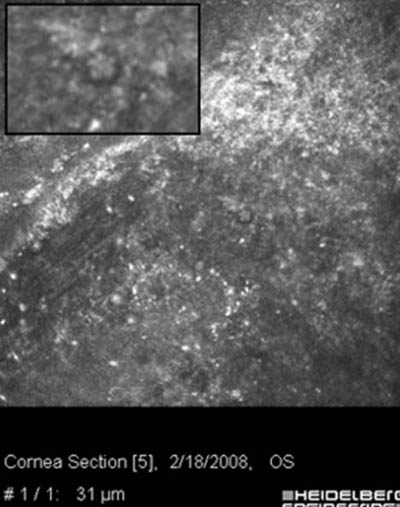

• Microscopia Confocal : 94 a 100% de especificidad y 80 a 84% de sensibilidad

Microscopía Confocal